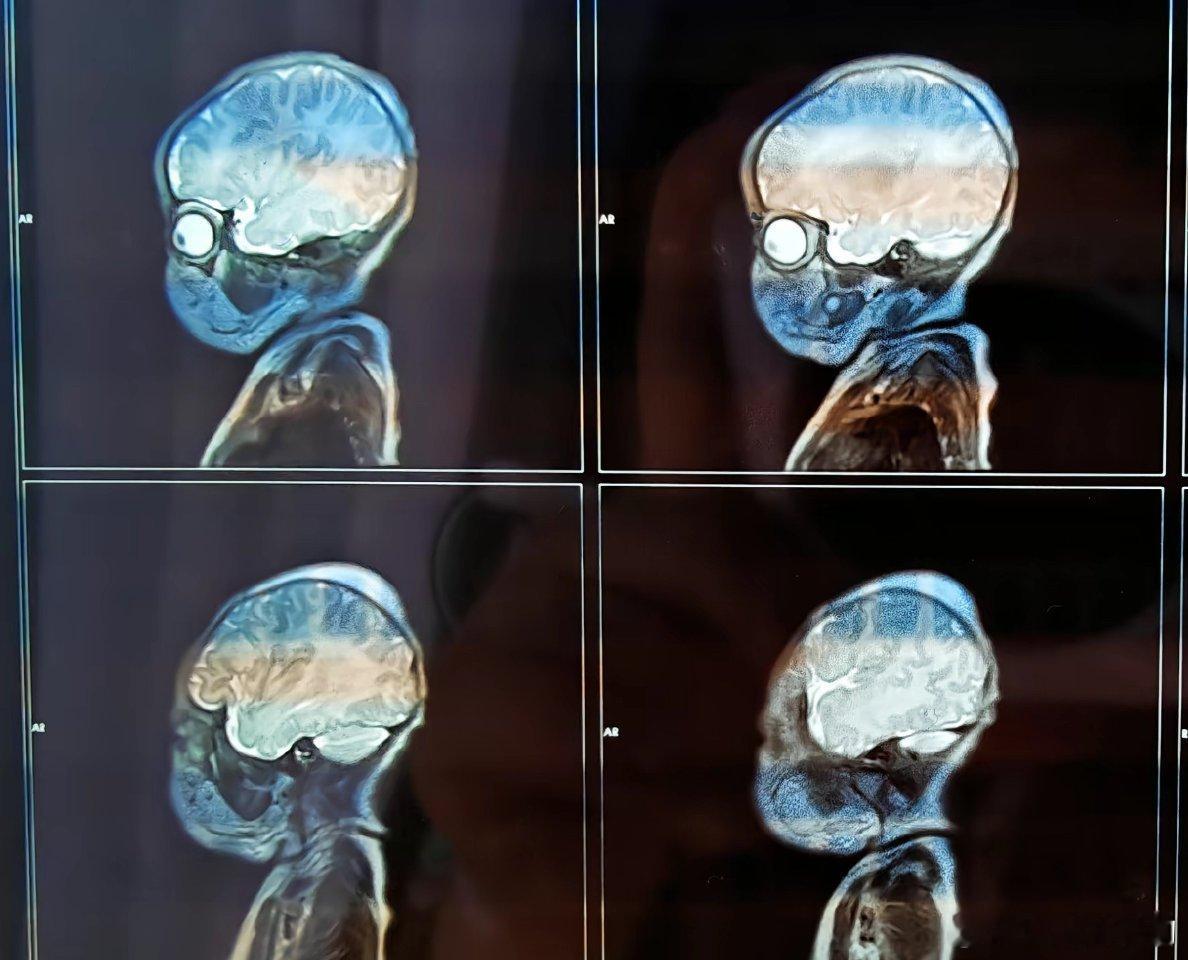

小婴儿的核磁共振全是脑子太可爱了!!!插画一样![哈哈][哈哈]